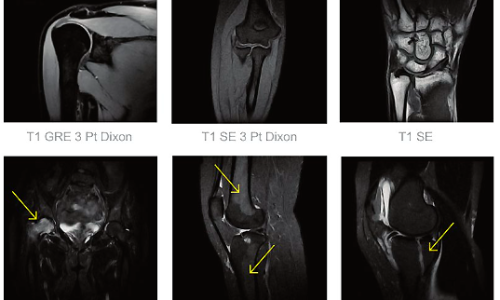

Risonanza Magnetica Aperta PICA MRI

L’apparecchiatura per Risonanza Magnetica aperta PICA, presente nel Centro OPTIMUM, racchiude innovazione ed ergonomia, con la sua architettura aperta unica, e le applicazioni cliniche all’avanguardia lo rendono ideale per il comfort del paziente, tempi di acquisizione rapidi ed eccellente qualità dell’immagine, con rumore minimo.

Risonanza Magnetica Aperta applicazioni principali

La Risonanza magnetica aperta RM è fondamentale per studiare in modo tridimensionale sia i tessuti molli che i duri e, grazie a procedure specifiche, facilita la diagnosi di varie patologie

Risonanza magnetica Spalla:** Analizza lesioni tendinee, muscolari e fibrocartilaginee.

Risonanza magnetica Bacino:** Valuta la struttura osteo-articolare per diverse condizioni tra cui patologie traumatiche e oncologiche.

Risonanza magnetica Anca:** Mediante mezzo di contrasto intra-articolare, esamina tendini, muscoli e legamenti.